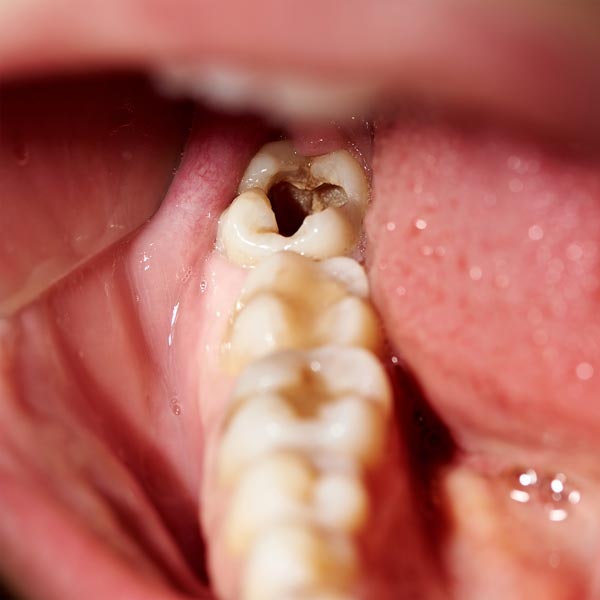

Do I Need a Tooth Extraction?

Severe pain, gum swelling, and visible tooth fractures can all be indicative of a serious dental problem. However, there is no way to know for sure if you need extraction unless you see a dentist for an exam.

If you suspect a problem with one or more of your teeth, contact our McKinney dental office as soon as possible. The sooner you see the dentist, the more likely we can provide treatment to save your natural teeth.